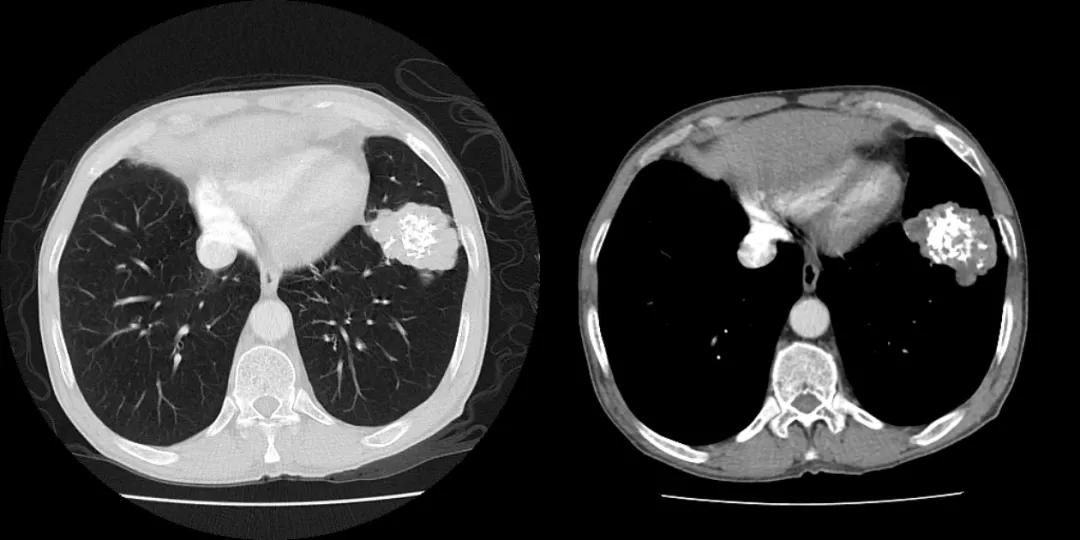

CASE 1

男性 61 岁,因呼吸困难和胸痛就诊,胸片提示左肺内占位;

典型爆米花样改变的肺内错构瘤